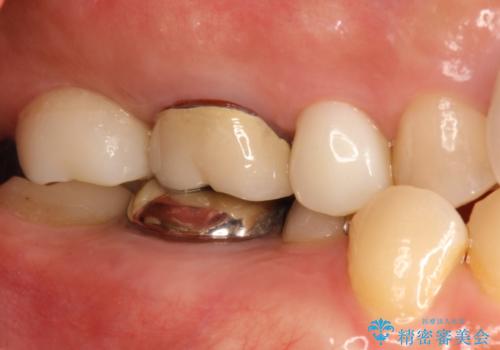

- 右上の奥歯がしみるとのことで確認すると、右上の一番奥の歯の銀歯の下が虫歯になっていました。

かなり大きな銀歯が装着されていたので、かぶせ物にて治療を行うこととなりました。

同時に右上の後ろから3番目の歯のかぶせ物も適合が悪かったので同時に治療することとなりました。